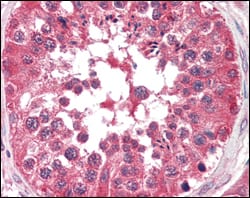

分类: 科研抗体货号: 20109别名: DYN2; DYNII; CMTDI1; CMTDIB; DI-CMTB; DNM2应用: IHC反应种属: Human

分类: 科研抗体货号: 20106别名: INHA; inhibin, alpha应用: IHC,IF反应种属: Human